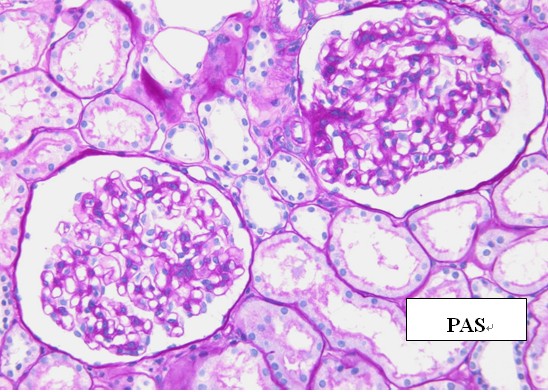

7. 组织固定脱水系列套装试剂的特殊组织染色实验:经该系列试剂脱水包埋制备的组织切片可以良好的进行特殊染色。

糖原染色

网状纤维染色 粘液染色